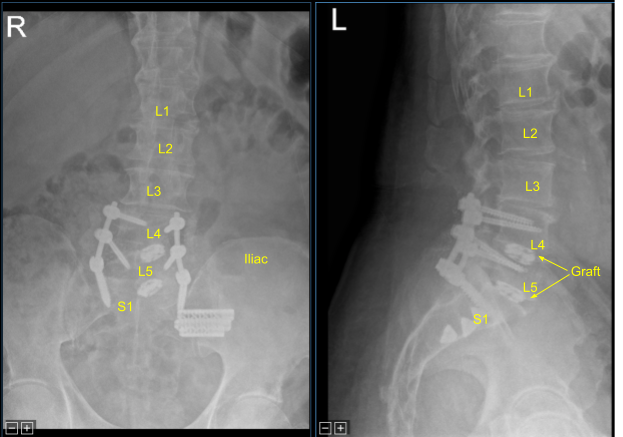

Precut-precontoured titanium rods were selected, contoured further and placed across the tulips from L4 to S1 bilaterally and secured with locking caps which were all final tightened with a torque and anti torque device. AP and lateral fluoroscopy was used to confirm appropriate sizing and positioning of the rods.

Next, morselized autograft resected from spinous processes of L4 and L5, which was morselized in the bone mill, was mixed with demineralized bone matrix allograft putty as well as bone morphogenic protein. We aspirated iliac crest bone marrow through a separate incision created for the Schanz pin with a bone marrow aspirator. This was mixed as well.

These were packed in lateral gutters and across the facet joints after decortication from L4 to S1 for arthrodesis.The wound was irrigated clear. Hemostasis was obtained with bipolar electrocautery and bone wax.